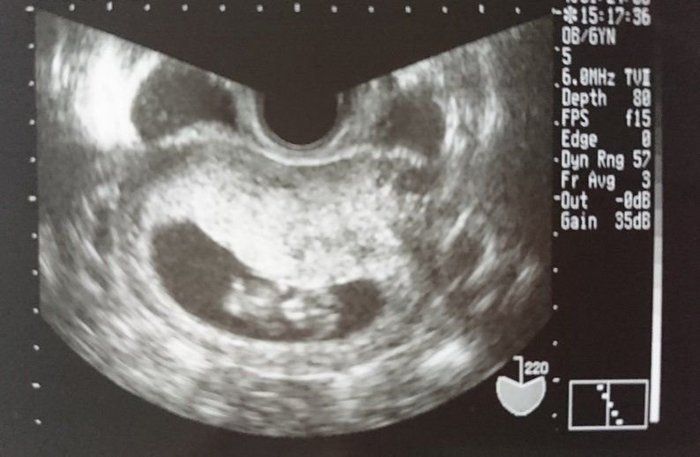

セイコさんの妊娠9週目のエコー写真 赤ちゃんぽくなって来ました

頭やおなか、短い手足も見えて来て、生き物っぽくなってきました。元気な姿を確認できるとほっとします。結果、問題はなかったのですが、私の体質的に子宮が大きくなる際に少し出血するようで、この頃はおりものに色がついているのが心配な日々でした。